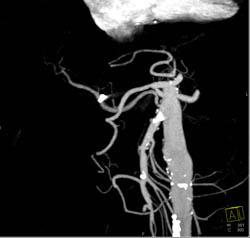

Focal Nodular Hyperplasia (FNH)